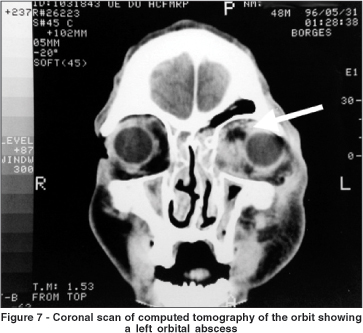

In order to categorize the radiological patterns of cellulitis the following guidelines were adopted. Diffuse fat infiltration was characterized by an increased density of the extra- or intraconal fat. The limits of the transition between the normal fat and the enhanced fat density were typically gradual and not well defined. A subperiosteal abscess was diagnosed when the periorbita was elevated from at least one orbital wall adjacent to a paranasal sinus. Finally, an orbital abscess was defined whenever an abnormal heterogeneous density was found (with or without ring appearance) within the orbital fat.

In all cases intraorbital changes could be detected. Diffuse infiltration was seen as an isolated feature in 11 patients (24.44%) who were successfully managed using medical treatment with intravenous antibiotics alone (Figure 4). As shown in Figure 5, subperiosteal abscesses were diagnosed in 28 patients (62.23%). The detached periosteum was usually well demarcated, defining the border of fluid collection. In 9 patients (20%) there was a diffuse fat infiltration at the boundaries of periorbita elevation (Figure 6). Orbital abscesses were seen in 6 patients (13.33%, Figure 7). All of these cases were surgically confirmed.

In our opinion, orbital abscesses should be drained without any delay. It is well known that intravenous antibiotics can penetrate the abscess(34), but without drainage their antibacterial activity within the abscess is poor, probably because the purulent milieu protects the microorganisms by enzymatic degradation of antibiotics(35-36). Therefore the risk of such cases to originate intracranial complications is high. In addition, an orbital abscess provokes a rapid expansion of the orbital contents, carrying a extremely high risk of visual impairment.